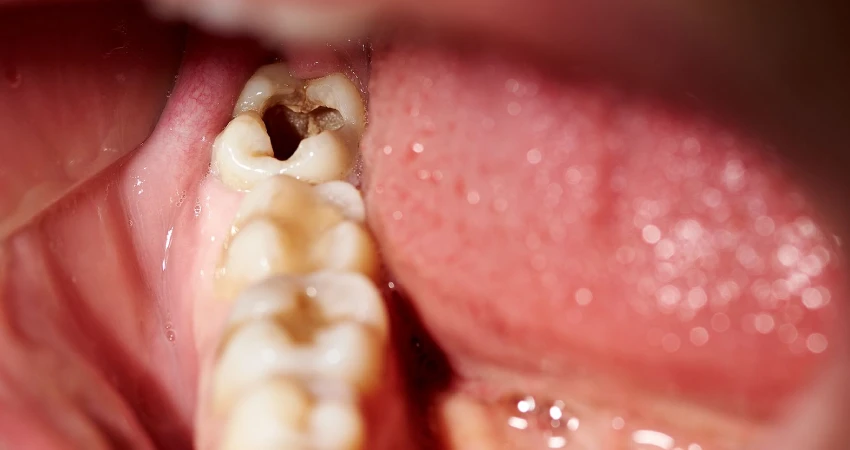

Deep dental caries is an advanced stage of tooth decay in which the lesion extends into the inner structures of the tooth, particularly the dentin and the dental pulp, which contains nerves and blood vessels. At this point, it often causes sharp pain and pronounced sensitivity when consuming hot or cold food and drinks.

In this stage, symptoms may include persistent toothache, bad breath, discoloration of the affected tooth, and in some cases swelling of the gums or face if the infection reaches the tooth roots.

As deep dental caries progress, symptoms become more evident, shifting from mild discomfort to persistent, troublesome pain.

One of the main warning signs is sharp or throbbing toothache, especially when consuming cold, hot, or sugary foods and drinks, with the pain sometimes continuing even after the stimulus is removed.

Patients may also notice increased tooth sensitivity, visible pits or cavities in the affected tooth or molar, and discoloration that may turn brown or even black.

In more advanced stages, pain may occur when biting or chewing due to pressure on the tooth, along with swelling and redness of the surrounding gum tissue, and potentially bad breath caused by bacterial buildup within the deep carious lesion.